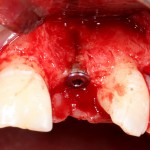

Например, в следующей ситуации:

Оставить так, как есть — это значит, сильно рисковать имплантом и объемом альвеолярного гребня — фактически, большая часть импланта пятого зуба «висит в воздухе». Поэтому получившуюся костную полость мы заполняем аутокостной стружкой в смеси с Bioss и закрываем коллагеновой мембраной BioGide:

При необходимости, мембрану можно фиксировать пинами.

Через три месяца результат:

можно ставить формирователи и заканчивать лечение:

В указанном выше случае использование костных блоков просто невозможно.